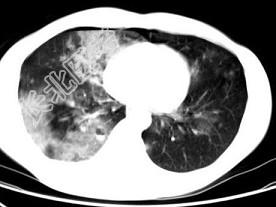

- 单项选择题男,28岁, 外伤后1小时,胸部CT如图, 最可能的诊断为 ( )

A、肺炎

B、肺脓肿

C、肺囊肿

D、肺癌

E、双肺挫伤